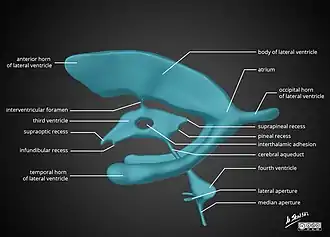

There are several foramina, openings acting as channels, that connect the ventricles. The interventricular foramina (also called the foramina of Monro) connect the lateral ventricles to the third ventricle through which the cerebrospinal fluid can flow.

| Name | From | To |

| interventricular foramina (Monro) | lateral ventricles | third ventricle |

| Cerebral aqueduct (Sylvius) | third ventricle | fourth ventricle |

| Median aperture (Magendie) | fourth ventricle | subarachnoid space via the cisterna magna |

| Right and left lateral apertures (Luschka) | fourth ventricle | subarachnoid space via the cistern of great cerebral vein |

The ventricles are filled with cerebrospinal fluid (CSF) which bathes and cushions the brain and spinal cord within their bony confines. CSF is produced by modified ependymal cells of the choroid plexus found in all components of the ventricular system except for the cerebral aqueduct and the posterior and anterior horns of the lateral ventricles. CSF flows from the lateral ventricles via the interventricular foramina into the third ventricle, and then the fourth ventricle via the cerebral aqueduct in the midbrain. From the fourth ventricle it can pass into the central canal of the spinal cord or into the subarachnoid cisterns via three small foramina: the central median aperture and the two lateral apertures. According to the traditional understanding of cerebrospinal fluid (CSF) physiology, the majority of CSF is produced by the choroid plexus, circulates through the ventricles, the cisterns, and the subarachnoid space to be absorbed into the blood by the arachnoid villi.

The fluid then flows around the superior sagittal sinus to be reabsorbed via the arachnoid granulations (or arachnoid villi) into the venous sinuses, after which it passes through the jugular vein and major venous system. CSF within the spinal cord can flow all the way down to the lumbar cistern at the end of the cord around the cauda equina where lumbar punctures are performed.

The cerebral aqueduct between the third and fourth ventricles is very small, as are the foramina, which means that they can be easily blocked.